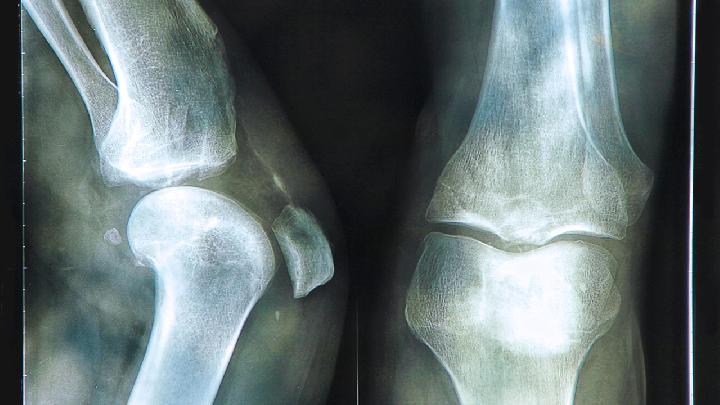

不少人对股骨头坏死这种疾病都很熟悉吧,该疾病的发生严重的影响到患者的身心健康,那么股骨头坏死病人会传染吗?只有了解引起的原因才能明白这个问题,有很多的原因都会引起该疾病的发生,下面就给打讲解股骨头坏死原因有哪些。